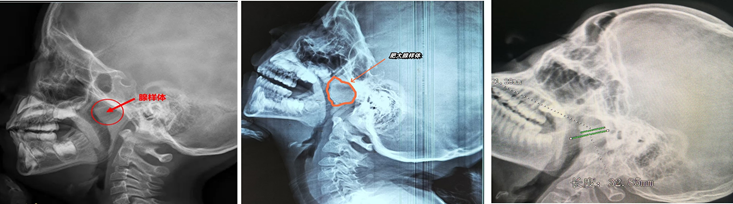

腺样体是位于鼻咽顶后部的一块较大的淋巴组织,也是人体的一个免疫器官,孩子出生以后它其实就存在了。它就像一个“小卫士”,守护着呼吸道的入口。

首先 观察症状:长期打呼噜、张口呼吸、听力下降等。其次到医院检查:医生可以用鼻内镜查看腺样体大小;或者X光或CT:评估腺样体堵塞程度(通常堵塞>70%需手术)。

① 鼻内镜检查:

评估是否存在腺样体肥大。Ⅰ度:腺样体堵塞后鼻孔≤25%;Ⅱ度:26%-50%;Ⅲ度:51-75%;Ⅳ度:>75%。

② 影像学检查:

鼻咽部侧位片示腺样体的宽度和鼻咽腔的宽度比值(A/N)≤0.6为正常范围;0.61≤A/N≤0.75中度肥大;A/N≥0.75为病理性肥大。